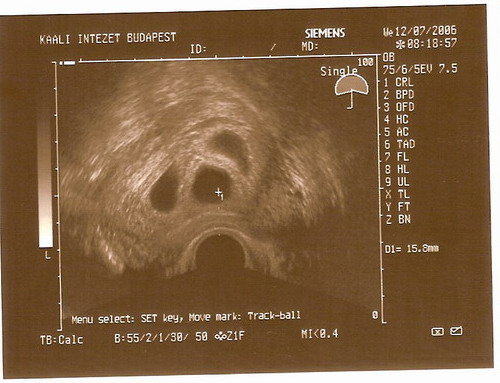

A tegnapi nap meg nagyon hosszú volt, és tartogatott ám meglepetést. Írtam nektek, hogy nálam a 2 baba az elég rizikós a méhnyak műtét miatt... Aztán felmásztam az ágyra, és már kerestem is a szememmel a fekete pöttyöt, amit most látnom kellene. Rá is jöttem egyből, hogy vmi nem stimmel, mert 2 pötty van, egy kicsi + egy nagy. Most akkor melyik a jó?! Nem vártam kettőt, mert 1 domináns tüsző volt, meg 2 kicsi. Aztán elmagyarázta a doktor úr, hogy itt viszont tényleg 2 baba tapadt meg, a nagyobban mutatta is a szikhólyagot, de a picike az nagyon picike, valószínűleg fel fog szívódni. Erre én teljesen beijedtem, mert ugye ez azért okozhat amott is galibát, a másik meg az, hogy most a szívem szakad bele, hogy a másik nem nőtt tövább... Lehet hogy az volt a baj, hogy egy petefészekben érett az összes tüsző, ugye aki először odaért a jó helyre, annak nagyobb esélye volt. Persze az agyam magyarázza, hogy arra az egy babára kell összpontosítani, de lehet hogy az a baj, hogy nem is vártam többet. Szóval furdal a lelkiismeret, féltem mindkettőt, egyiket a másiktól, nem merek örülni, pedig egyébként meg boldogság és melegség van a szívemben.

De itt úgysem tehetek semmit, próbálok optimista lenni, jövő héten megyek újra uh-ra. Később kellene, de szabadságra megy az orvosom, és még ő akarja megnézni (ez nagyon megnyugtat). Képet majd próbálok feltenni, de az enyémen még csak kis pötty van, a szikhólyag a monitoron látszott, de a képen nem. De azért nagyon szép kép, imádom.